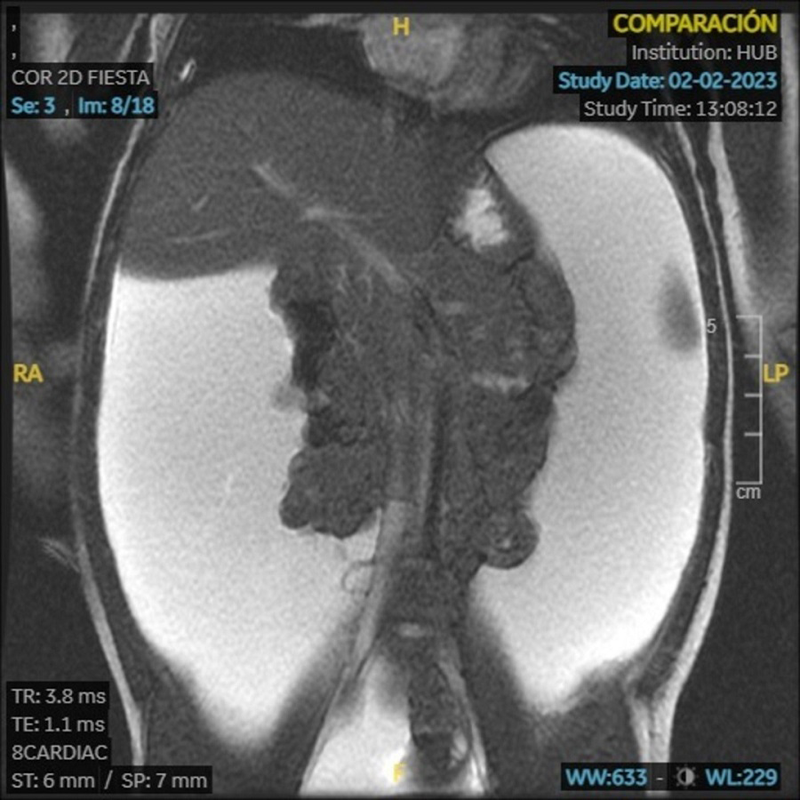

Ni­ña de 2 a­ños con dis­ten­sión ab­do­mi­nal. ¿En qué de­be­mos pen­sar?

Niña de 2 años con distensión abdominal de meses de evolución. No astenia. Buen apetito. No coluria, acolia, ni otra clínica. Peso: 12,3 kg. Talla: 86 cm. Abdomen distendido con cambio de matidez con la postura. Resto sin interés.

Examen analítico con hemograma, perfil hepatorrenal, metabolismo férrico, fólico, B12 y estudio de coagulación normales; marcadores de enfermedad celíaca negativos.